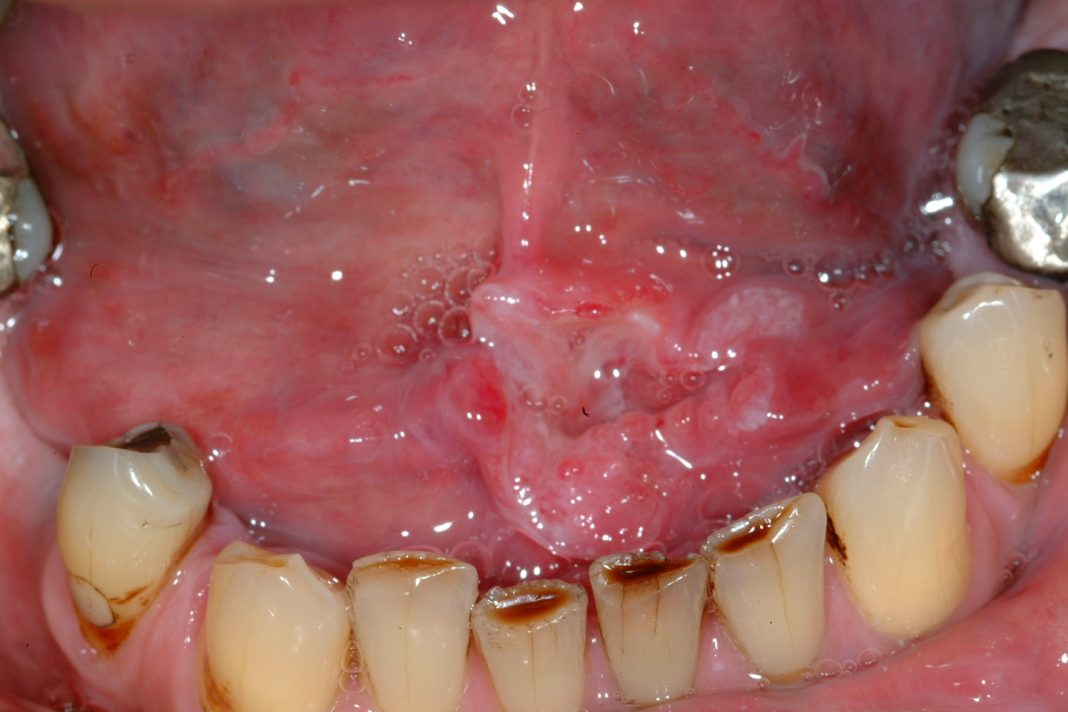

Es común que muchas personas experimenten mal aliento por la mañana, debido a la reducción del flujo salival durante el sueño, lo que permite que las bacterias se multipliquen en la boca. Además, la acumulación de restos de comida durante la noche contribuye al problema. Esto puede causar incomodidad al despertar y afectar las interacciones tempranas del día. Mantener una buena higiene bucal antes de dormir y al despertar puede ayudar a mitigar este problema.